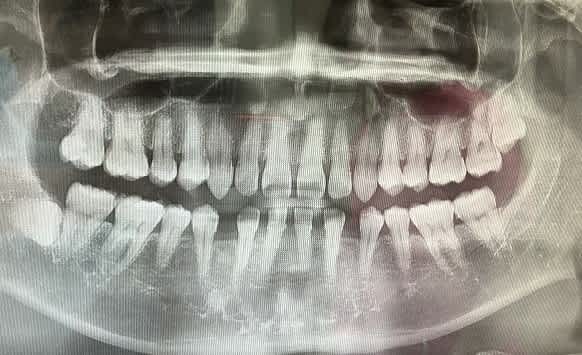

初診なので一応全部検査するとのことでレントゲンを撮られる

親知らずがいますが、もう出てこないでしょうとのこと。

歯の数が普通の人と比べて足りません。抜けたわけでもなくそういう人だそうです。

なので僕の歯はスカスカなのです。フレディ・マーキュリーの逆です。

なお、スカスカを直すには治療期間2年半で約120万円かかるそうです。